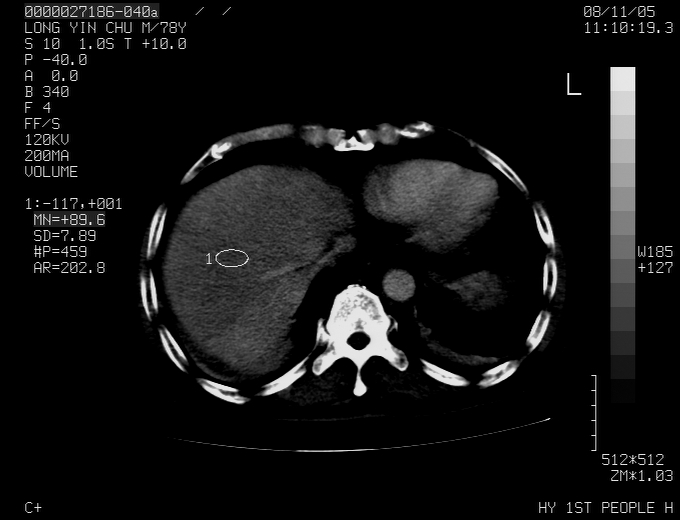

标题: CT16532:M78Y,肝脏病变,请会诊 [打印本页]

标题: CT16532:M78Y,肝脏病变,请会诊

腹胀,腹痛就诊,男性,78岁,外院b超未见异常。

肝ca,脾肾转移

考虑弥漫性肝癌并脾及双肾转移.双侧胸水.

图片质量欠佳:多考虑:左侧肾癌。脾脏转移!胸膜转移!

肝脾肾转移瘤可能性大,左肾不除外梗塞,双侧胸水

考虑弥漫性肝癌并脾及双肾转移,双侧胸水。

考虑肝癌并双肾及脾脏转移;双侧胸腔积液。